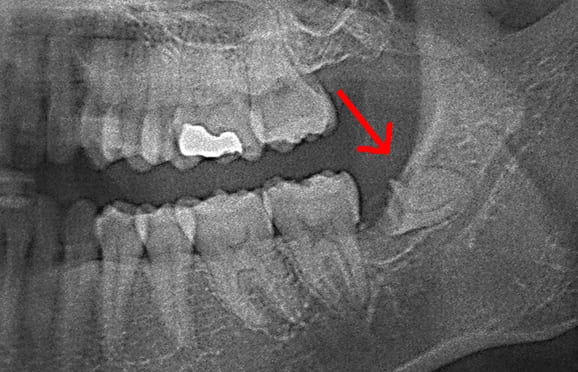

当院の院長は勤務医時代、親知らず専門外来にて診療にあたっていたので、顎の骨の中に埋まっている親知らずも抜歯いたします。難症例では、神経損傷リスクを抑えるため、2回法にて親知らずを抜く場合もあります。

● 下の顎の親知らず抜歯 2回法

藤沢デンタルオフィスの親知らず抜歯

01 神経に近い位置に親知らずの根が存在

02 親知らずの頭の部分だけ抜歯

03 親知らずの根の部分が神経から離れる

下の顎の親知らずの抜歯では、神経の損傷リスクを考えて2回に分けて抜歯する場合があります。 また、麻酔が効きにくい場合にも、同様に2回に分けて抜歯します。